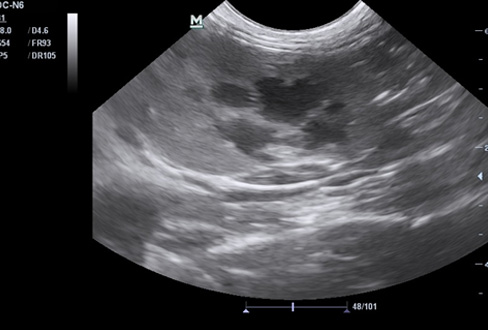

В сентябре 2018 года на плановый осмотр обратилась владелица кота Бони, возраст 8 лет. Во время диспансеризации была проведена ультразвуковая диагностика брюшной полости, по результатам которой была обнаружена патологическая структура на левой почке размером 2,0*1,5 см. Был поставлен предварительный диагноз – киста почки.

Для подтверждения диагноза с согласия владельцев была проведена пункция образования с аспирацией (откачиванием) жидкости под контролем УЗИ, под общей анестезией. После аспирации УЗ-картина левой почки соответствует норме. Аспирированная жидкость была отправлена в лабораторию на цитологическое исследование. По результатам цитологического исследования образование было идентифицировано как неинфицированная киста.